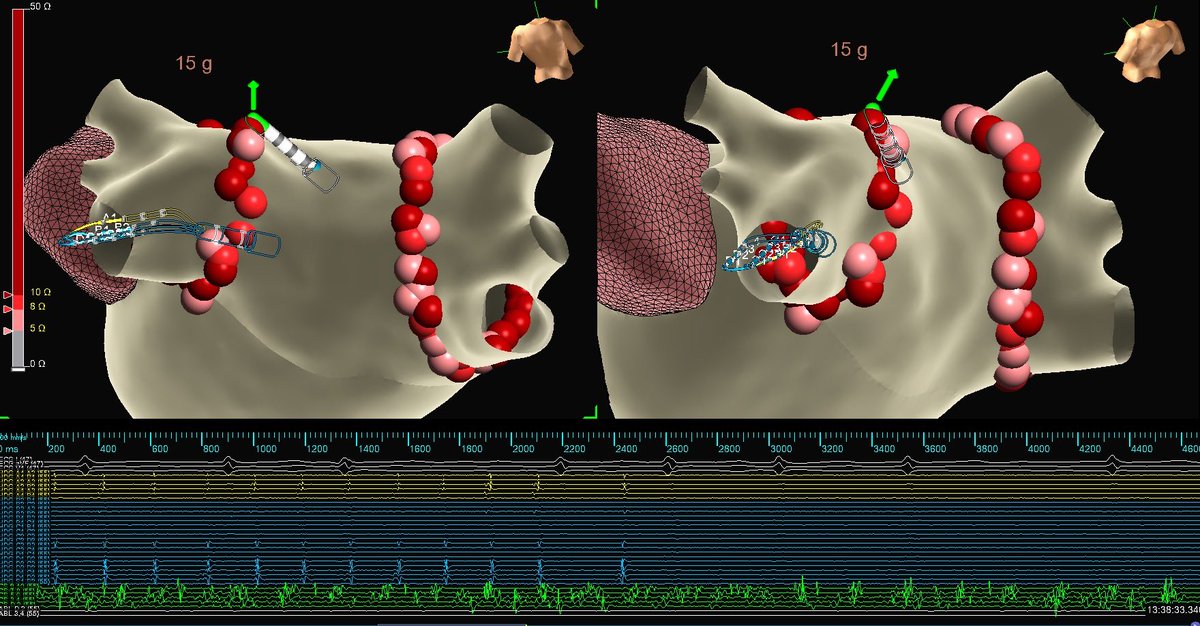

AVRT! Open window mapping of a concealed left lateral accessory pathway using the HD Grid. One burn term (1.3 seconds). #AbbottProud #MapMoreBurnLess #HDGrid #TactiFlex

SoFloAbbottEP's tweet image. AVRT! Open window mapping of a concealed left lateral accessory pathway using the HD Grid. One burn term (1.3 seconds).

#AbbottProud #MapMoreBurnLess #HDGrid #TactiFlex